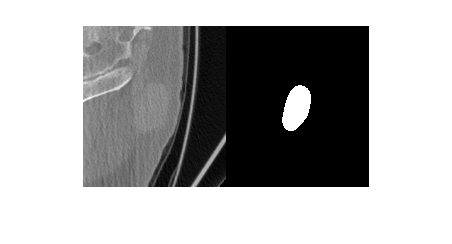

Visualize a slice of the CT image volume and the corresponding ROI.

figure

imshowpair(data.Voxels(:,:,20),roi.Voxels(:,:,20),"montage")